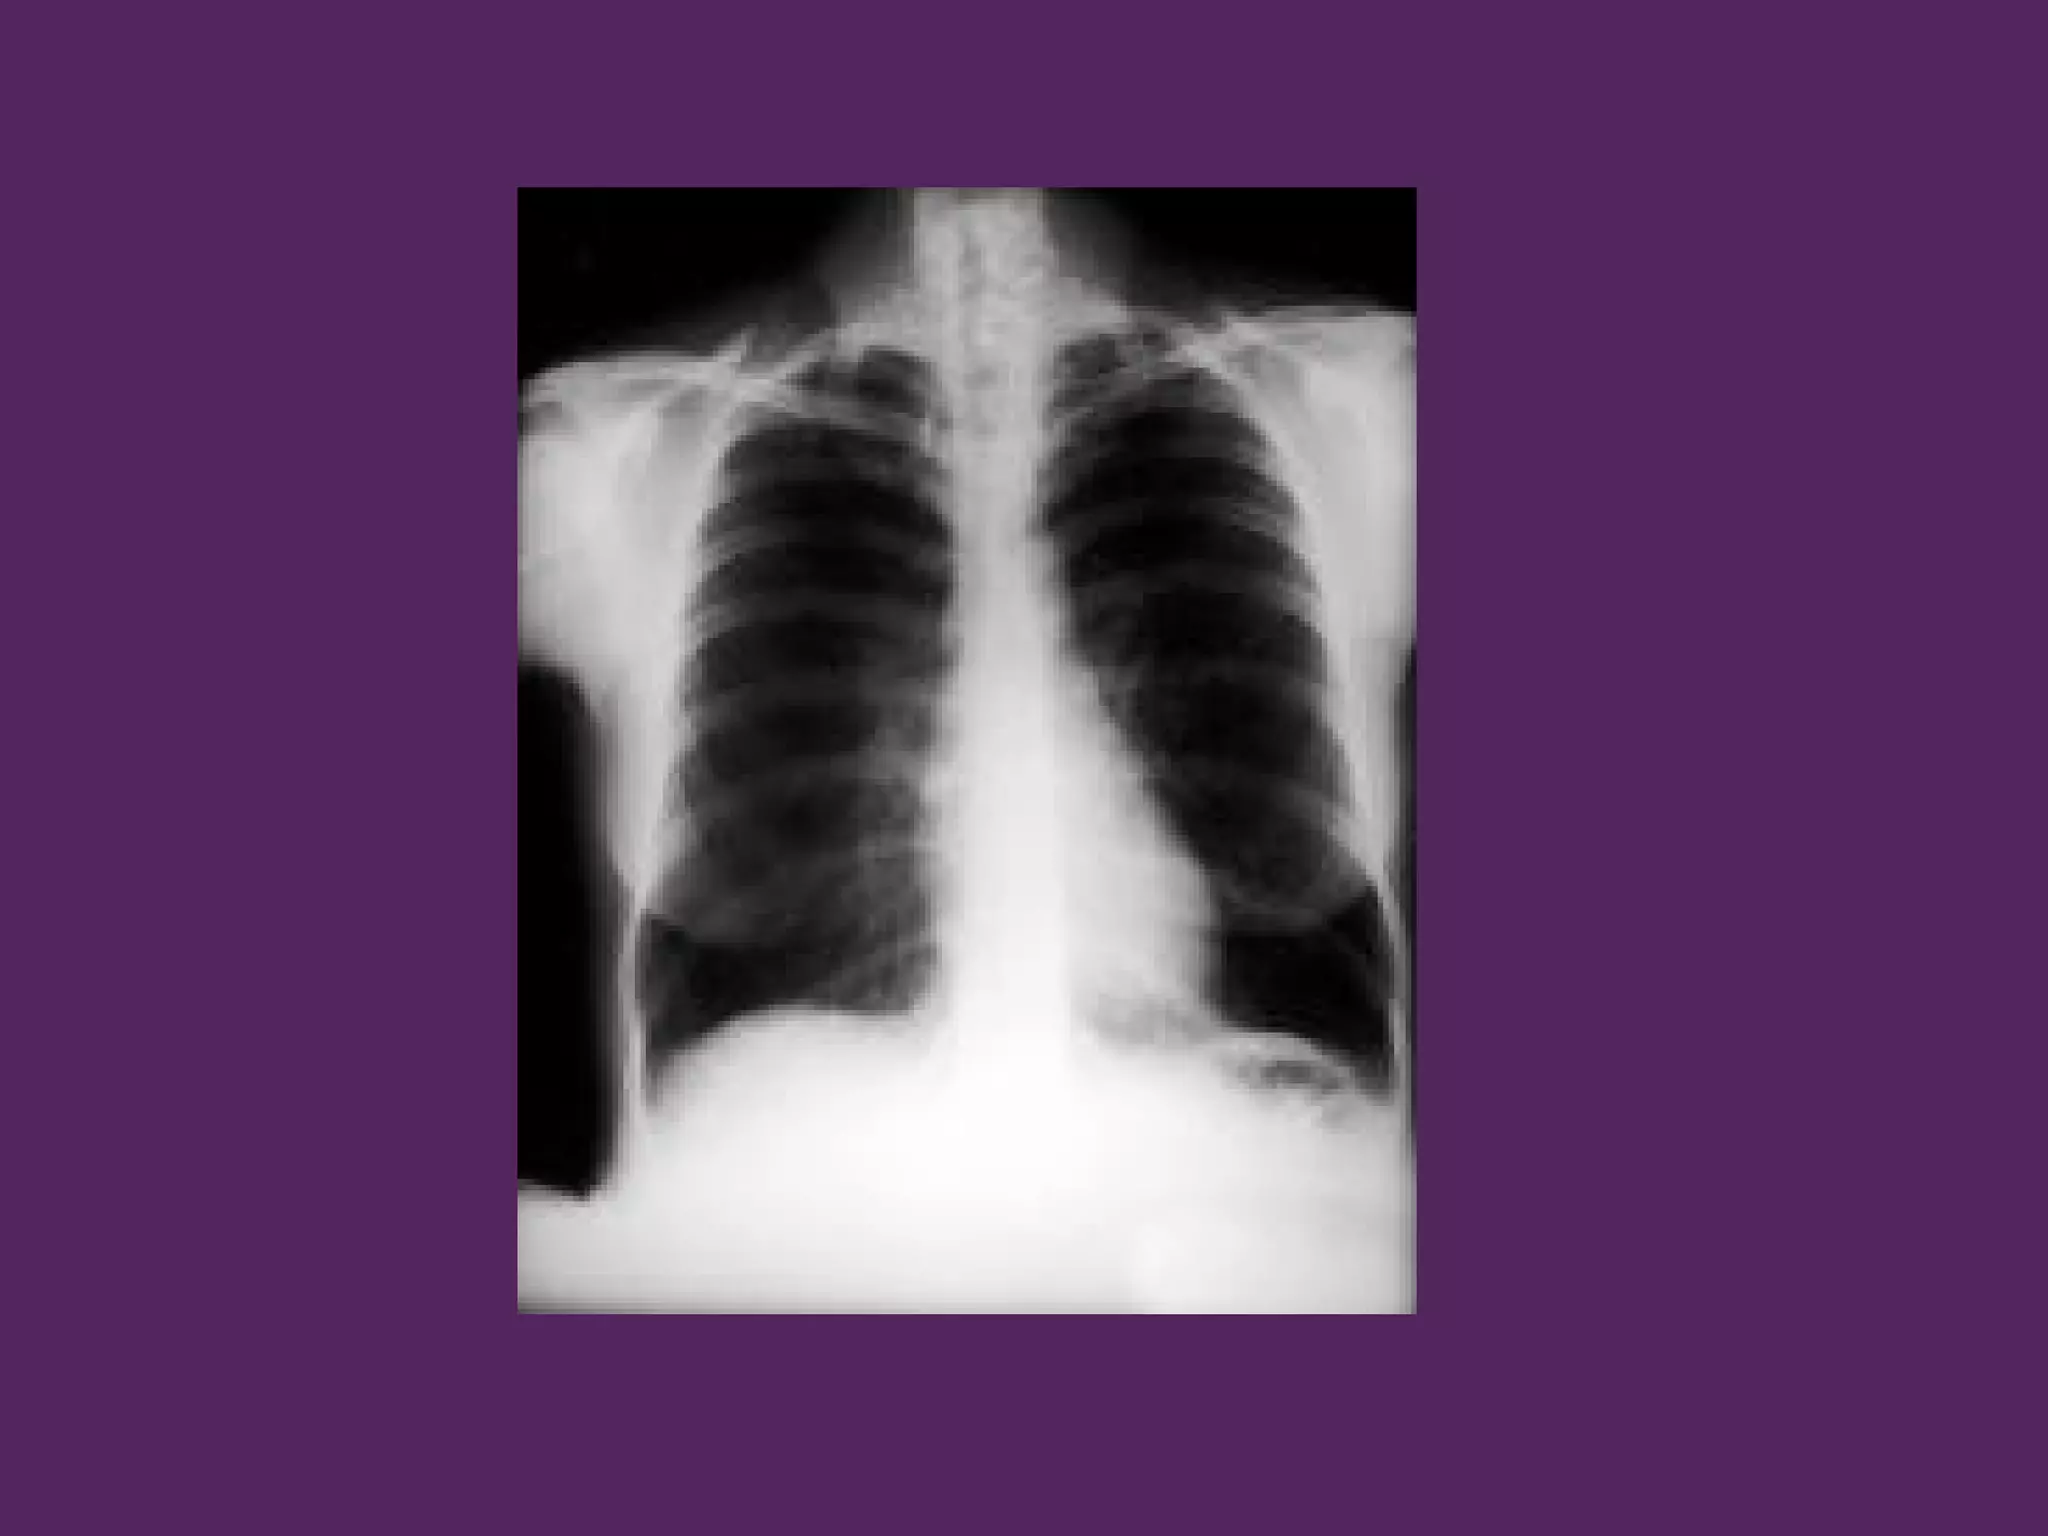

HÌNH ẢNH HỌC

- Căng dãn lồng ngực

- Tăng sáng phế trường

- Giảm số lượng mạch máu

HÌNH ẢNH HỌC -Căng dãn lồng ngực - Tăng sáng phế trường - Giảm số lượng mạch máu